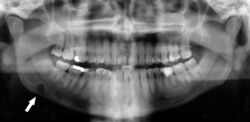

Dental panoramic radiograph showing dentigerous cyst (arrowed).

Orthopantomograms (OPTs) are used by health care professionals to provide information on:

• Impacted wisdom teeth diagnosis and treatment planning - the most common use is to determine the status of wisdom teeth and trauma to the jaws.